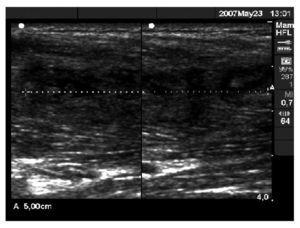

El estudio ecográfico mostró de nuevo colección anecoica de 5 × 10 (fig. 2) y la imagen de RM puso de manifiesto una colección purulenta en el tercio proximal de tensor del músculo de la fascia lata (fig. 3).

Figura 2 Imagen anecoica de bordes bien delimitados compatible con absceso muscular en el tensor de la fascia lata.

Se realizó de nuevo punción y aspiración dirigida. El cultivo y el antibiograma mostraron estafilococos coagulasa negativos sensibles al trimetoprim/sulfa-metoxazol. Tras 10 días de tratamiento el paciente estaba completamente asintomático, y a pesar de las imágenes ecográficas que se muestran en la figura 4, se le permitió volver a la competición.

Figura 4 Imagen hipoecoica de tejido cicatricial de reparación de 5 cm de eje mayor longitudinal en el músculo tensor de la fascia lata.